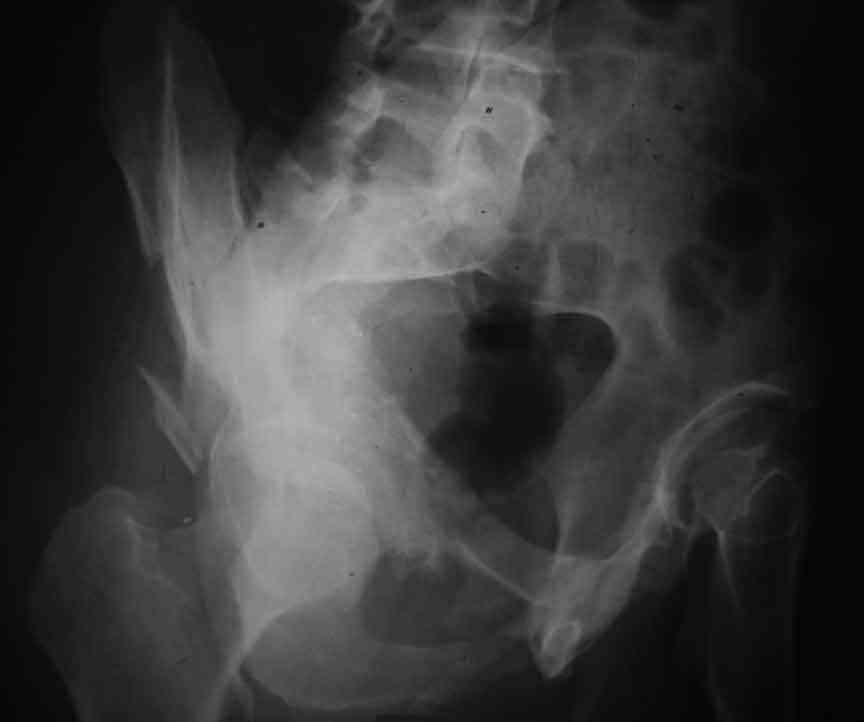

Dear Friends This is a 57 y old male.

Your input is welcome as to the classification of this fratcure, as well as the proposed management.

Dear Sir it looks quite difficult classify this fracture because the iliac view is not so clear.

In my opinion it is a column fracture because the obturator foramen is interrupted. There is a fracture of the posterior wall. If we assume the ap view as an iliac view it could be an anterior comun fracture plus posterior wall. It is difficult also to judge the head of the femur.

From the x rays it appears like a bicolumnar fracture with iliac extension (AO C1).

CT scan is mandatory to evaluate such fractures more accurately and also to plan the treatment and surgery Most of the bicolumnar fractures of the high variety in experienced hands can be managed thro the ilioinguinal approach

I am sending another iliac view, and a marked version of the AP I already sent. In this AP, the

proximal part of the greater sciatic notch as well as the distal parts of the ilioischial and iliopubic lines are marked with a grey interrupted line. A white interrupted line marks what could be an exit through the obturator foramen, or so I assume.